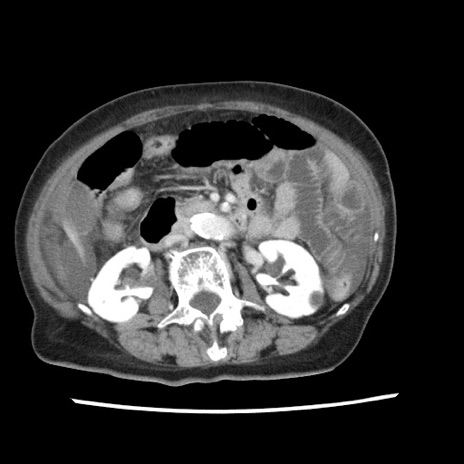

症例1(横断像)

【症例】80歳代女性

【主訴】腹痛

【現病歴】8時間前から腹痛あり来院。

【既往歴】糖尿病、脂質異常症、子宮体癌にて子宮全摘術

【身体所見】意識清明・会話良好だが腹痛で苦悶様、全腹部にわたって反跳痛と圧痛あり

【データ】WBC 13600、CRP 0.14、LDH 224、CK 90